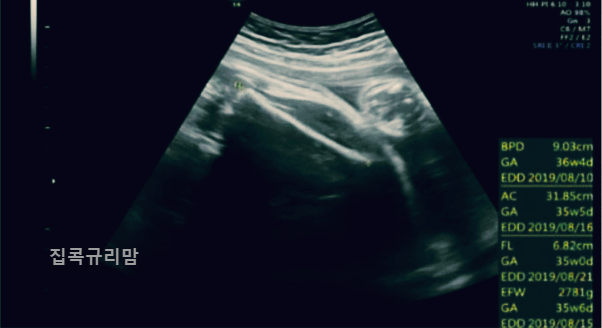

오늘은 태아초음파 아기초음파 용어에 대해 포스팅하려고 하는데요, 임신하게 되면 주기적으로 병원에서 초음파를 보는데 여러 용어들이 가득한 초음파를 볼 수 있습니다. 계속 초음파를 보다보면 용어가 궁금해지더라고요. 첫째 때 공부(?)를 하긴 했는데 역시나 기억이 사라져서 ㅎㅎ 'EDD'정도만 기억에 남아있는 제 모습을 발견했습니다. ㅎㅎ

초음파 용어가 엄청 많은데요, 가장 자주 볼 수 있는 용어들 위주로 정리하겠습니다.

GA(Gestational Age)

임신 주수로 W는 주수를, D는 날짜를 뜻합니다.

예시: 6w3d (6주 3일)

EDD (Expected Date of Delivery)

GA를 기준으로 산출한 출산 예정일로 GA와 EDD는 태아 크기에 따라 매번 달라질 수 있는데, 보통 임신 12주 미만에 정해진 임신 주수와 분만 예정일을 기준으로 태아 성장을 평가합니다.

AC(Abdominal Circumference)

BPD(Biparietal Diameter)

FL(Femur Length)

EBW(Estimated Body Weight): 태아의 현재 체중을 확인합니다.